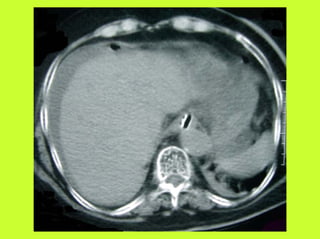

3) RADIO (PNO)

RADIOGRAPHIES

ABDOMEN SP -scanner

AUTRES EXAMENS

"TOGD aux hydrosolubles?

" Echo, scanner

" Coelioscopie ?

RADIOGRAPHIES ABDOMEN SP -scanner PNEUMOPERITOINE SUR SUJET DEBOUT " Croissant gazeux sous diaphragmatique " Disparition du niveau hydroaérique gastrique PNEUMOPERITOINE SUR SUJET COUCHE " Visibilité du ligament triangulaire du foie " Visibilité anormale des parois intestinales " Image aérique pré-hépatique "Pneumatisation de MORRISSON (cul de sac inter-hépato-rénal) AUTRES EXAMENS "TOGD aux hydrosolubles? " Echo, scanner " Coelioscopie ? " Pas de lavement colique, pas de fibroscppie, pas de coloscopie, pas d’IRM